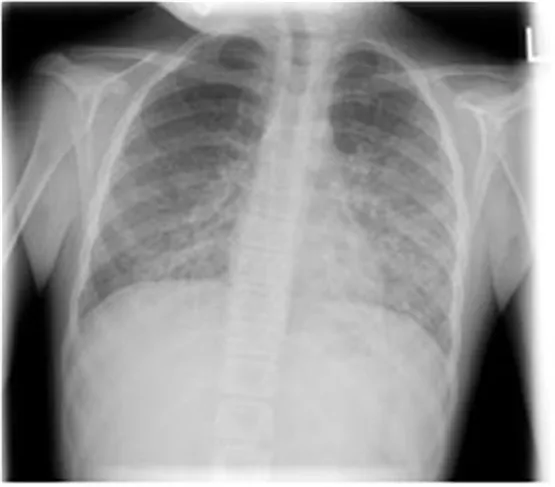

7세 여아가 급성 림프구성 백혈병 치료 중인 환자로, 최근에 발열과 함께 기침 증상이 나타나 병원을 방문하였다. 환자의 맥박은 분당 123회, 호흡은 분당 36회, 체온은 39.1℃로 측정되었다. 청진 결과 수포음은 들리지 않았으며, 콧물 검사에서 호흡기 바이러스는 음성으로 나왔다. 다음은 환자의 검사 결과이다. 흉부 X선 사진이다. 이 환자에게 적절한 치료는 무엇인가?

ALL 치료를 받고 있는 7세 여아에서 발열, 기침, 빈맥(HR 123), 빈호흡(RR 36) 및 저산소혈증(SpO2 88%, PaO2 80mmHg)을 나타나고 있다. 호흡기 바이러스에 대한 콧물 검사 음성을 통해 바이러스성 원인을 R/O할 수 있으며, ALL 치료로 인한 면역 저하 상태(WBC 1,600)와 CXR에서 interstitial pneumonia 양상을 고려할 때 진균 및 PJP(Pneumocystis jirovecii pneumonia)을 의심할 수 있다.

- CXR : 양측 폐문 부위에서 대칭적인 미만성 망상 결절 음영 시작 -> 말초 폐야를 향해 폐포 경화로 진행